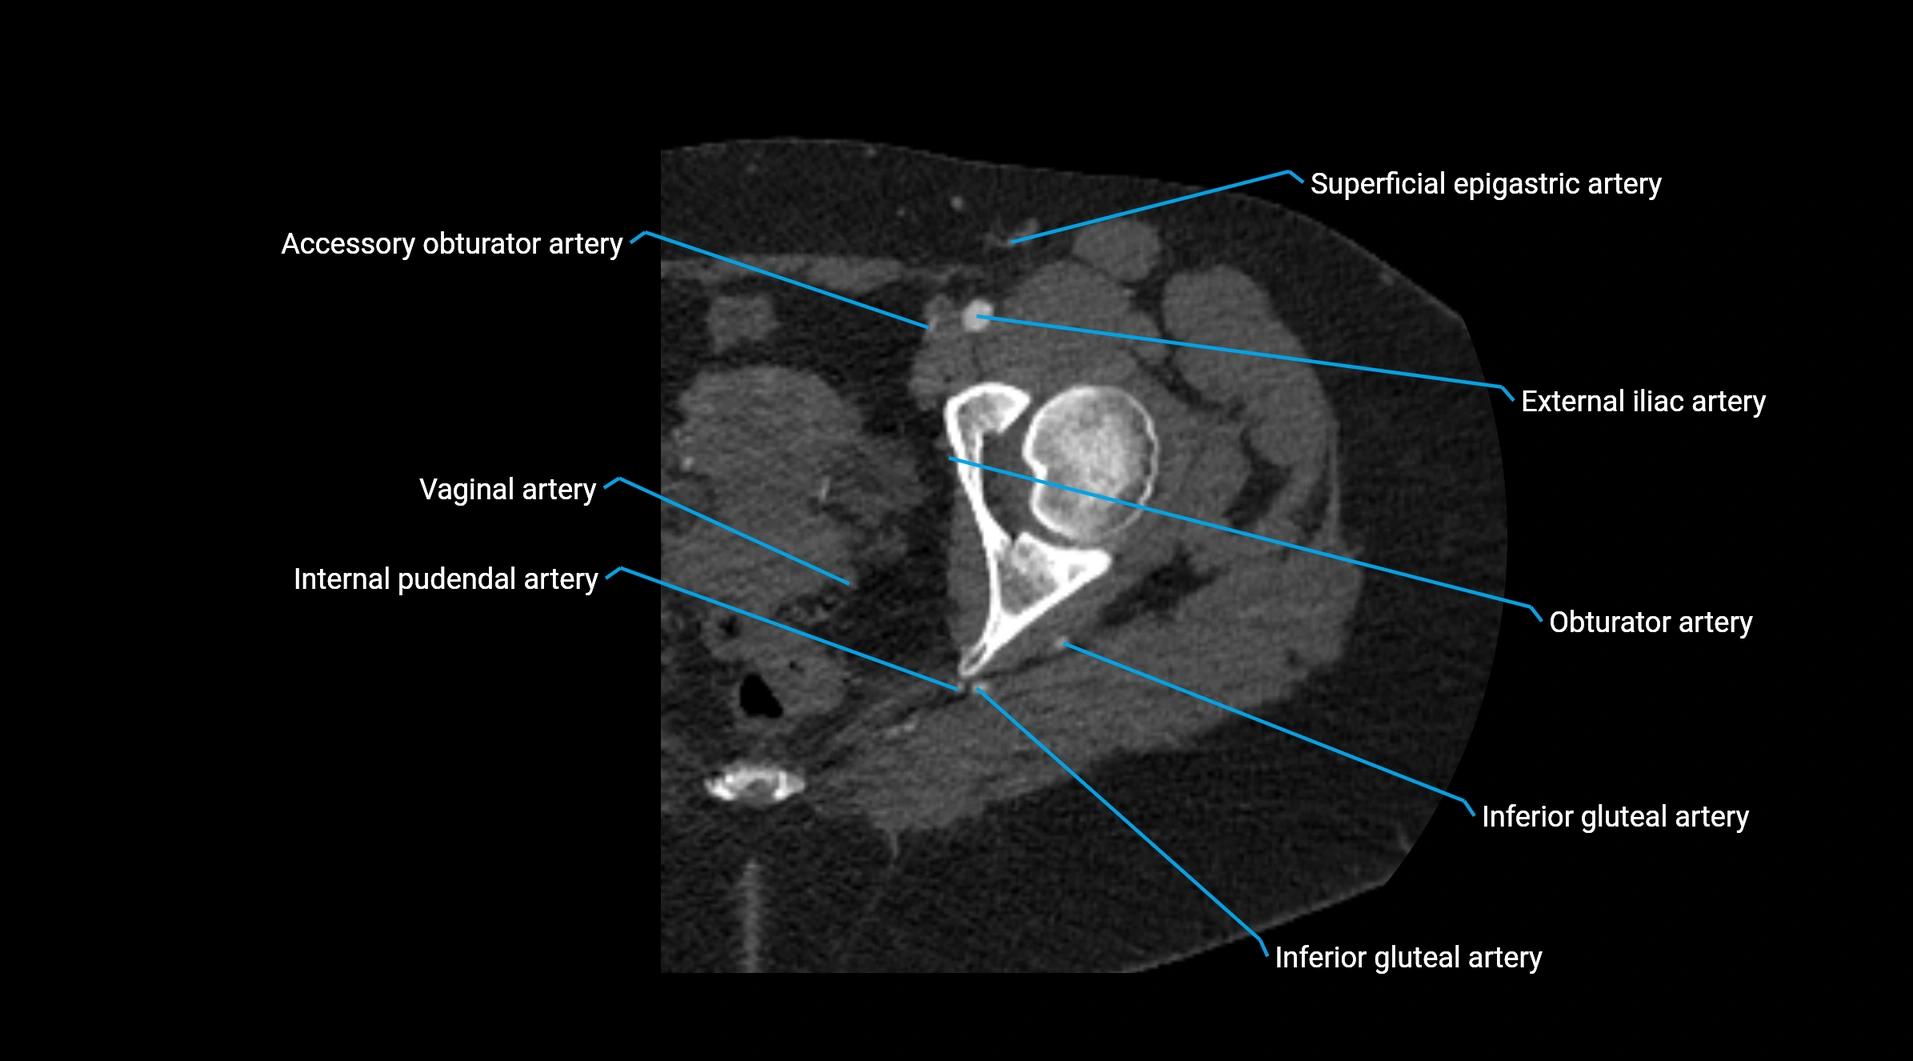

The abdominal aorta is the continuation of the thoracic aorta, beginning at the level of the aortic hiatus of the diaphragm (T12 vertebra) and terminating at the level of the L4 vertebra where it bifurcates into the right and left common iliac arteries. It lies slightly to the left of the midline and courses anterior to the vertebral bodies, surrounded by the retroperitoneal structures of the abdomen.

The abdominal aorta gives off numerous visceral and parietal branches, supplying the abdominal organs, pelvic structures, and lower limbs. It is the main conduit of oxygenated blood from the heart to the abdomen and lower body. The aorta is clinically significant as the common site of aneurysm, dissection, atherosclerosis, and traumatic injury.

Branches

• Unpaired visceral branches: celiac trunk, superior mesenteric artery (SMA), inferior mesenteric artery (IMA)

• Paired visceral branches: middle suprarenal arteries, renal arteries, gonadal arteries (testicular or ovarian)

• Parietal branches: inferior phrenic arteries, lumbar arteries, median sacral artery

• Terminal branches: right and left common iliac arteries